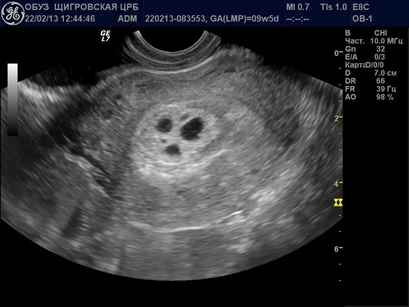

Эксперты в области акушерства и гинекологии подчеркивают, что пузырчатый занос является серьезным осложнением беременности, требующим внимательного подхода к диагностике и лечению. Основные признаки заболевания включают аномально высокий уровень ХГЧ, отсутствие сердцебиения плода и характерные изменения на УЗИ, такие как наличие пузырьков в матке. Для точной диагностики врачи рекомендуют проводить комплексное обследование, включая ультразвуковое исследование и анализы крови. Важно отметить, что ранняя диагностика позволяет избежать серьезных осложнений и выбрать оптимальную тактику лечения, что особенно актуально для сохранения здоровья женщины и ее будущих беременностей.

| УЗИ-картина «снежного шара» или «гроздь винограда» | Очень высокая | |

Диагностика с помощью УЗИ: Одним из основных методов диагностики пузырчатого заноса является ультразвуковое исследование. На УЗИ можно увидеть характерные «пузырьки» в матке, которые представляют собой скопления аномальных тканей. Это позволяет врачам быстро и точно определить наличие заболевания.

Для исследования пузырчатого заноса применяются анализы крови, вагинальное обследование и УЗИ. Благодаря современным технологиям, с помощью ультразвука можно легко определить наличие такого заболевания. После проведения операции и лечения, врачи наблюдают за состоянием женщины и проводят разные обследования.

Чтобы увидеть, как выглядит пузырчатый занос, можно посмотреть фото в интернете. Обычно на ультразвуковом исследовании четко видны пузыри, которые располагаются внутри матки. Как можно понять, при таких изменениях в органе, развитие здорового плода не может происходить.

Когда на УЗИ можно увидеть пузырный занос?

Виды пузырного заноса. Выявляется чаще такая патология на сроках 10-12 недель гестации. Содержит такой пузырный занос диплоидное количество хромосом 46 ХХ. При этом стоит сказать, что все хромосомы являются отцовскими. Может быть и кариотип 46 ХУ, однако Х и У также являются отцовскими.